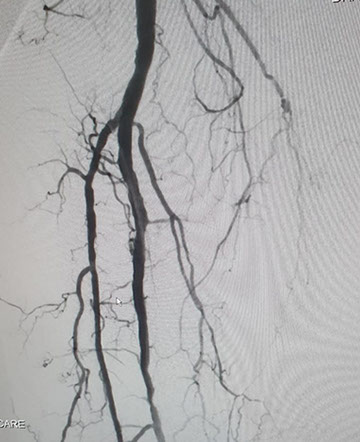

El Dr Sergio Raul Ludueña Jefe del Servicio de Hemodinamia de INCOR nos comentó sobre procedimiento realizado en el día de ayer en en el Servicio. "Queremos compartir con ustedes si bien no es un caso coronario , es un paciente obeso mórbido, diabético, con amputación supracondilea de miembro inferior izquierdo hace 3 años y actualmente con isquemia critica de miembro inferior derecho, con oclusión de ambas tíbiales y sin circulación en el pie".

Se realizó un abordaje híbrido con el Dr. Alejandro Flores, y se re canalizó ambas arterias tíbiales. Procedimiento inédito en nuestra provincia.

Las imágenes siguientes son previas al procedimiento y posterior se ve ambas arterias tíbiales permeables, y circulación en el pie